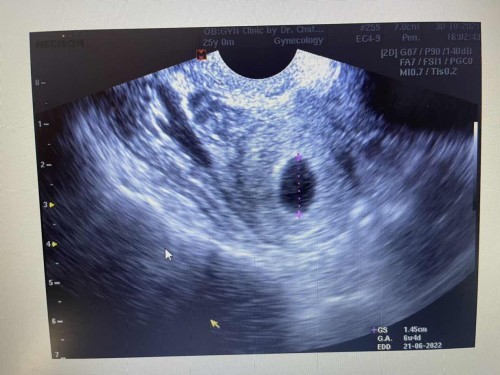

สวัสดีค่ะ ครรภ์6week4วัน เจอแค่ถุงการตั้งครรภ์+ถุงไข่แดง ผิดแกติไหมคะ กังวลว่าจะท้องลม อยากมีลูกมากๆๆๆๆ ขอคำแนะนำสำหรับคุณแม่หน่อยค่ะ เราพึ่ง ท้องแรก

ครร6สัปดาห์เจอแต่ถุงการตั้งครรภ์กับไข่แดงถือว่าผิดปกติไหมคะ